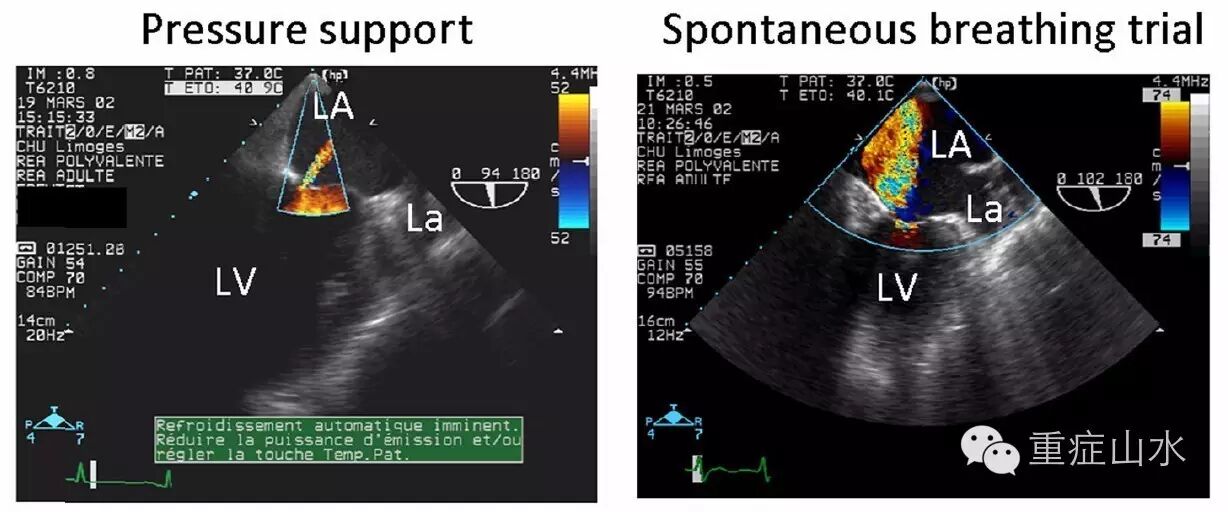

Fig. 2 Transesophageal echocardiographic hemodynamic monitoringin a patient with a known ischemic cardiomyopathy who failed ventilator weaning.Under pressure support, a trivial mitral regurgitation was disclosed by colorDoppler mapping in the two-chamber view (upper left), and leftcardiac filling pressures were low, as reflected by an inverted mitral E/ADoppler pattern (middle left) and a predominant pulmonary vein S wave (lower left). During thespontaneous breathing trial, a severe mitral regurgitation occurred (upper right), mitralDoppler pattern was restrictive (middle right), and pulmonary vein Doppler disclosed a reversed D waveconsistent with massive mitral insufficiency (lower right, arrow). The acute mitralregurgitation was attributed to a papillary muscle dysfunction secondary to atransient myocardial ischemic event. LA left atrium, La left auricle, LV left ventricle.Adapted from [7]

二尖瓣反流量在SBT时显著增加,可能导致脱机失败(Fig. 2)。